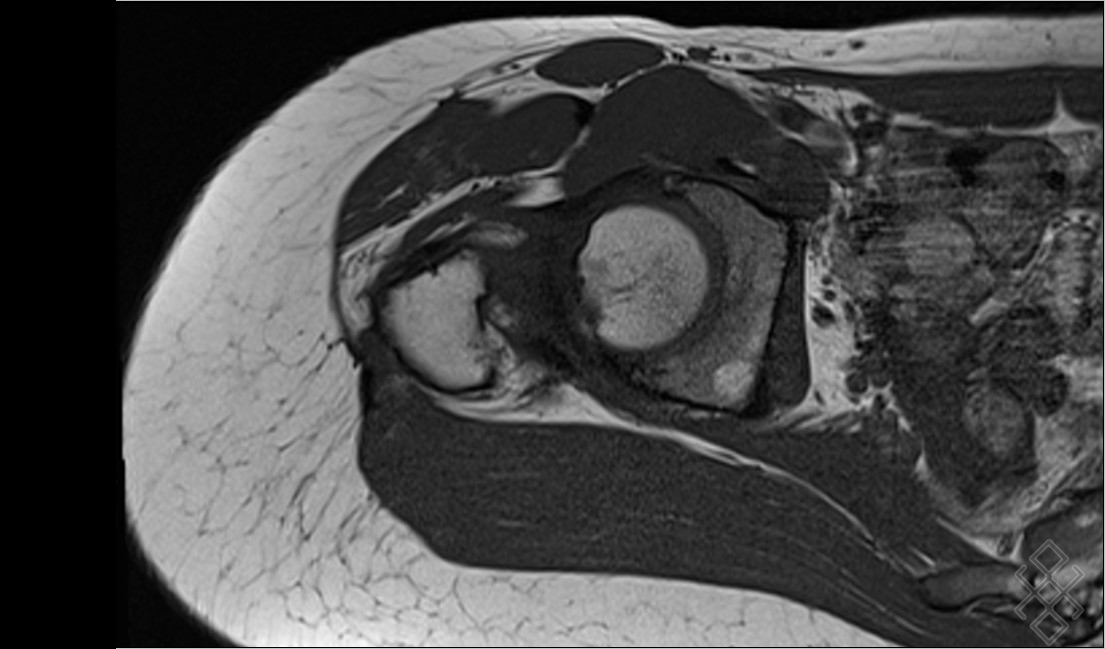

Pourtant, leurs répercussions sur l'activité physique et sur la rééducation du patient sont souvent importantes et méritent d'être à ce titre connues et reconnues.… L'IRM du bassin et des hanches est un examen de seconde intention après, dans la majorité des cas, un bilan radiographique simple et parfois une échographie

IRM Dole 39 Centre d'examens IRM à Dole (Jura) Centre d'imagerie par résonance magnétique. Il permet en particulier de rechercher : une inflammation des tendons (tendinite) des muscles gluteaux (fessiers) Une arthropathie de hanche (atteinte de l'articulation entre le fémur et le bassin) un épanchement dans l'articulation coxo. Nous vous conseillons de prévoir généralement une quarantaine